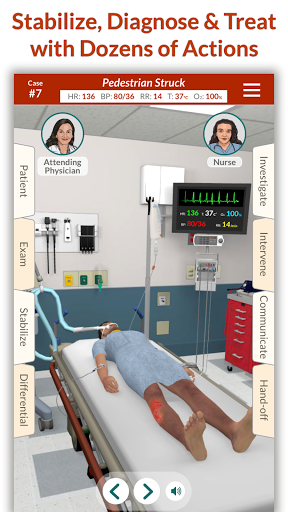

Đào tạo mô phỏng theo yêu cầu của Full Code với các bệnh nhân ảo thực tế cho phép bạn thực hành các trường hợp phức tạp và nâng cao kỹ năng của mình bất cứ khi nào bạn có thời gian nghỉ ngơi, bất kể bạn ở đâu, trên các thiết bị bạn đã sở hữu. CẢI THIỆN SỰ TỰ TIN

Các trường hợp có thể lặp lại vô hạn của Full Code đo lường các kỹ năng trong cả chẩn đoán và quản lý, cho phép bạn học hỏi từ những sai lầm của mình trong một môi trường không có rủi ro. Xây dựng năng lực để bạn có thể đối mặt với các trường hợp thực tế phức tạp một cách tự tin.

Mỗi trường hợp đều là một thách thức mới trong Full Code: từ chẩn đoán thông thường đến các bệnh hiếm gặp. Bạn không chỉ giới hạn ở bệnh viện—Full Code đã mở rộng sang nội dung trước khi nhập viện và EMS. Ra khỏi khoa cấp cứu và vào xe cứu thương để ứng phó với mọi tình huống mới!

Bệnh nhân và cảnh của chúng tôi trông và âm thanh chân thực hơn bao giờ hết.

• Cải tiến trường hợp chấn thương & quần áo đường phố

Chúng tôi đã cập nhật tất cả các trường hợp chấn thương với các hoạt động ổn định phù hợp hơn. Bệnh nhân chấn thương bây giờ bắt đầu trong trang phục đường phố!